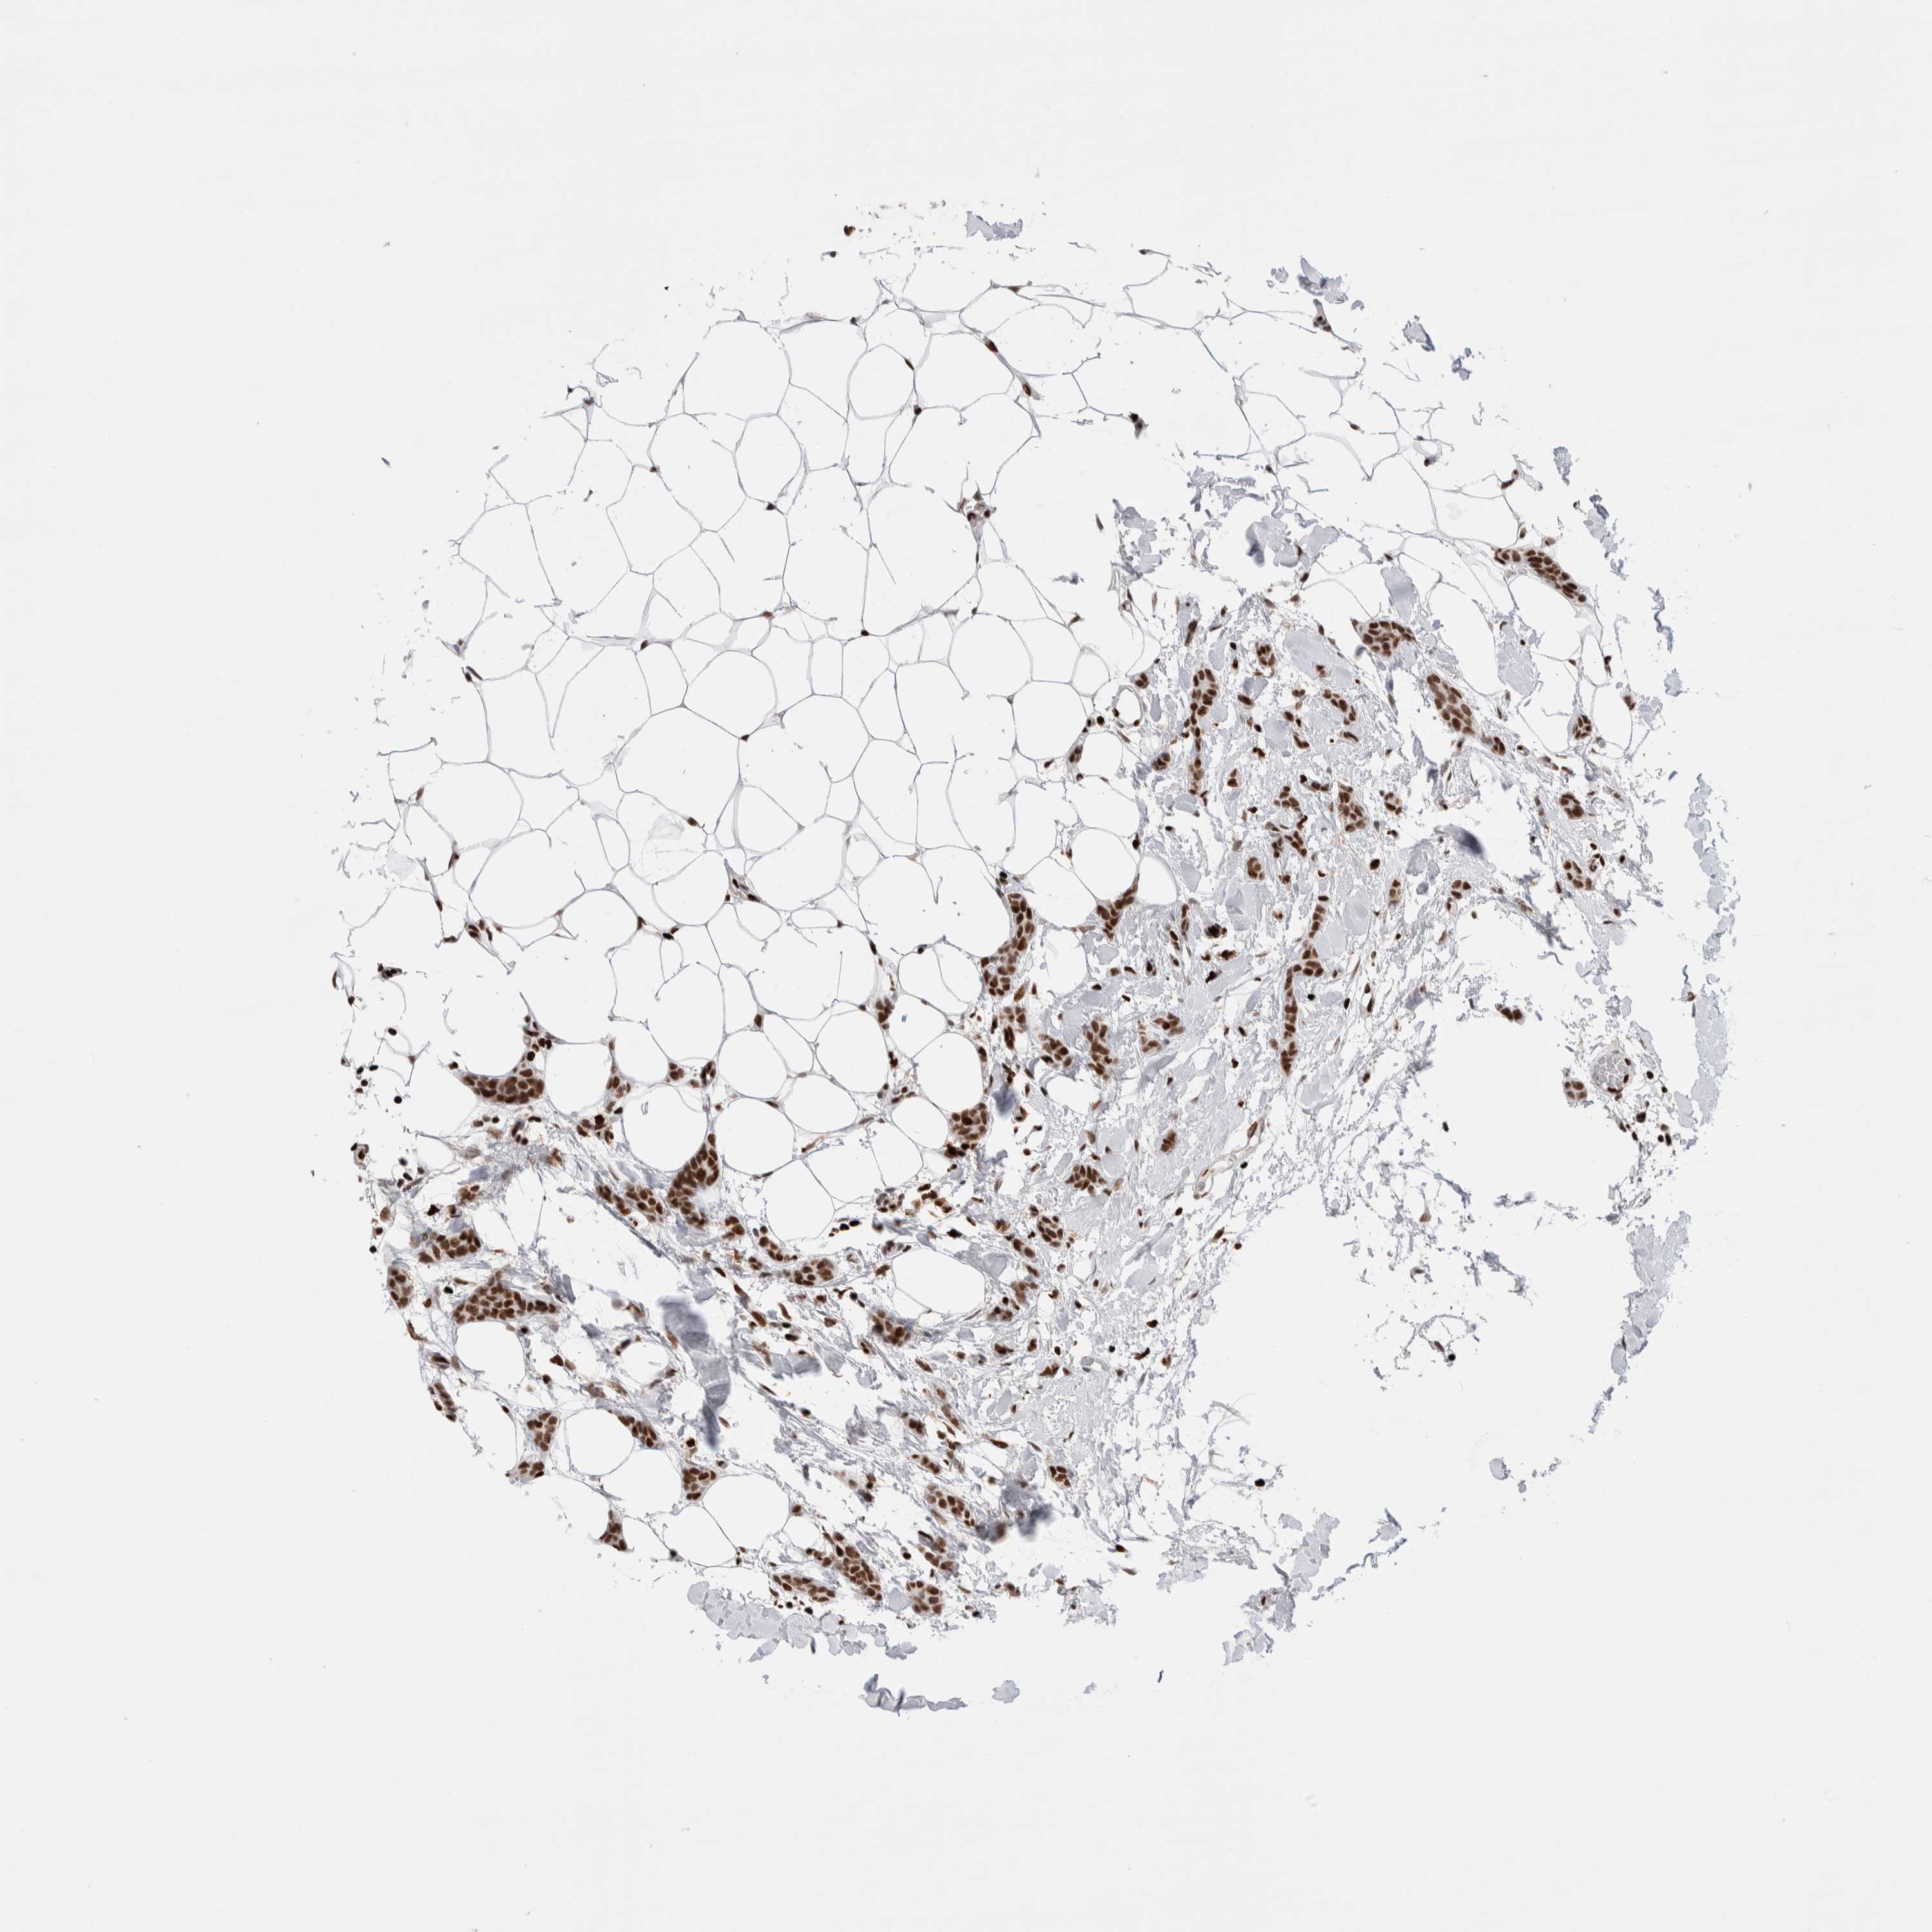

CANCER BREAST CANCER Show tissue menu

BRCA TCGA BRCA VALIDATION PROTEIN EXPRESSION

Breast cancer

Human cancer